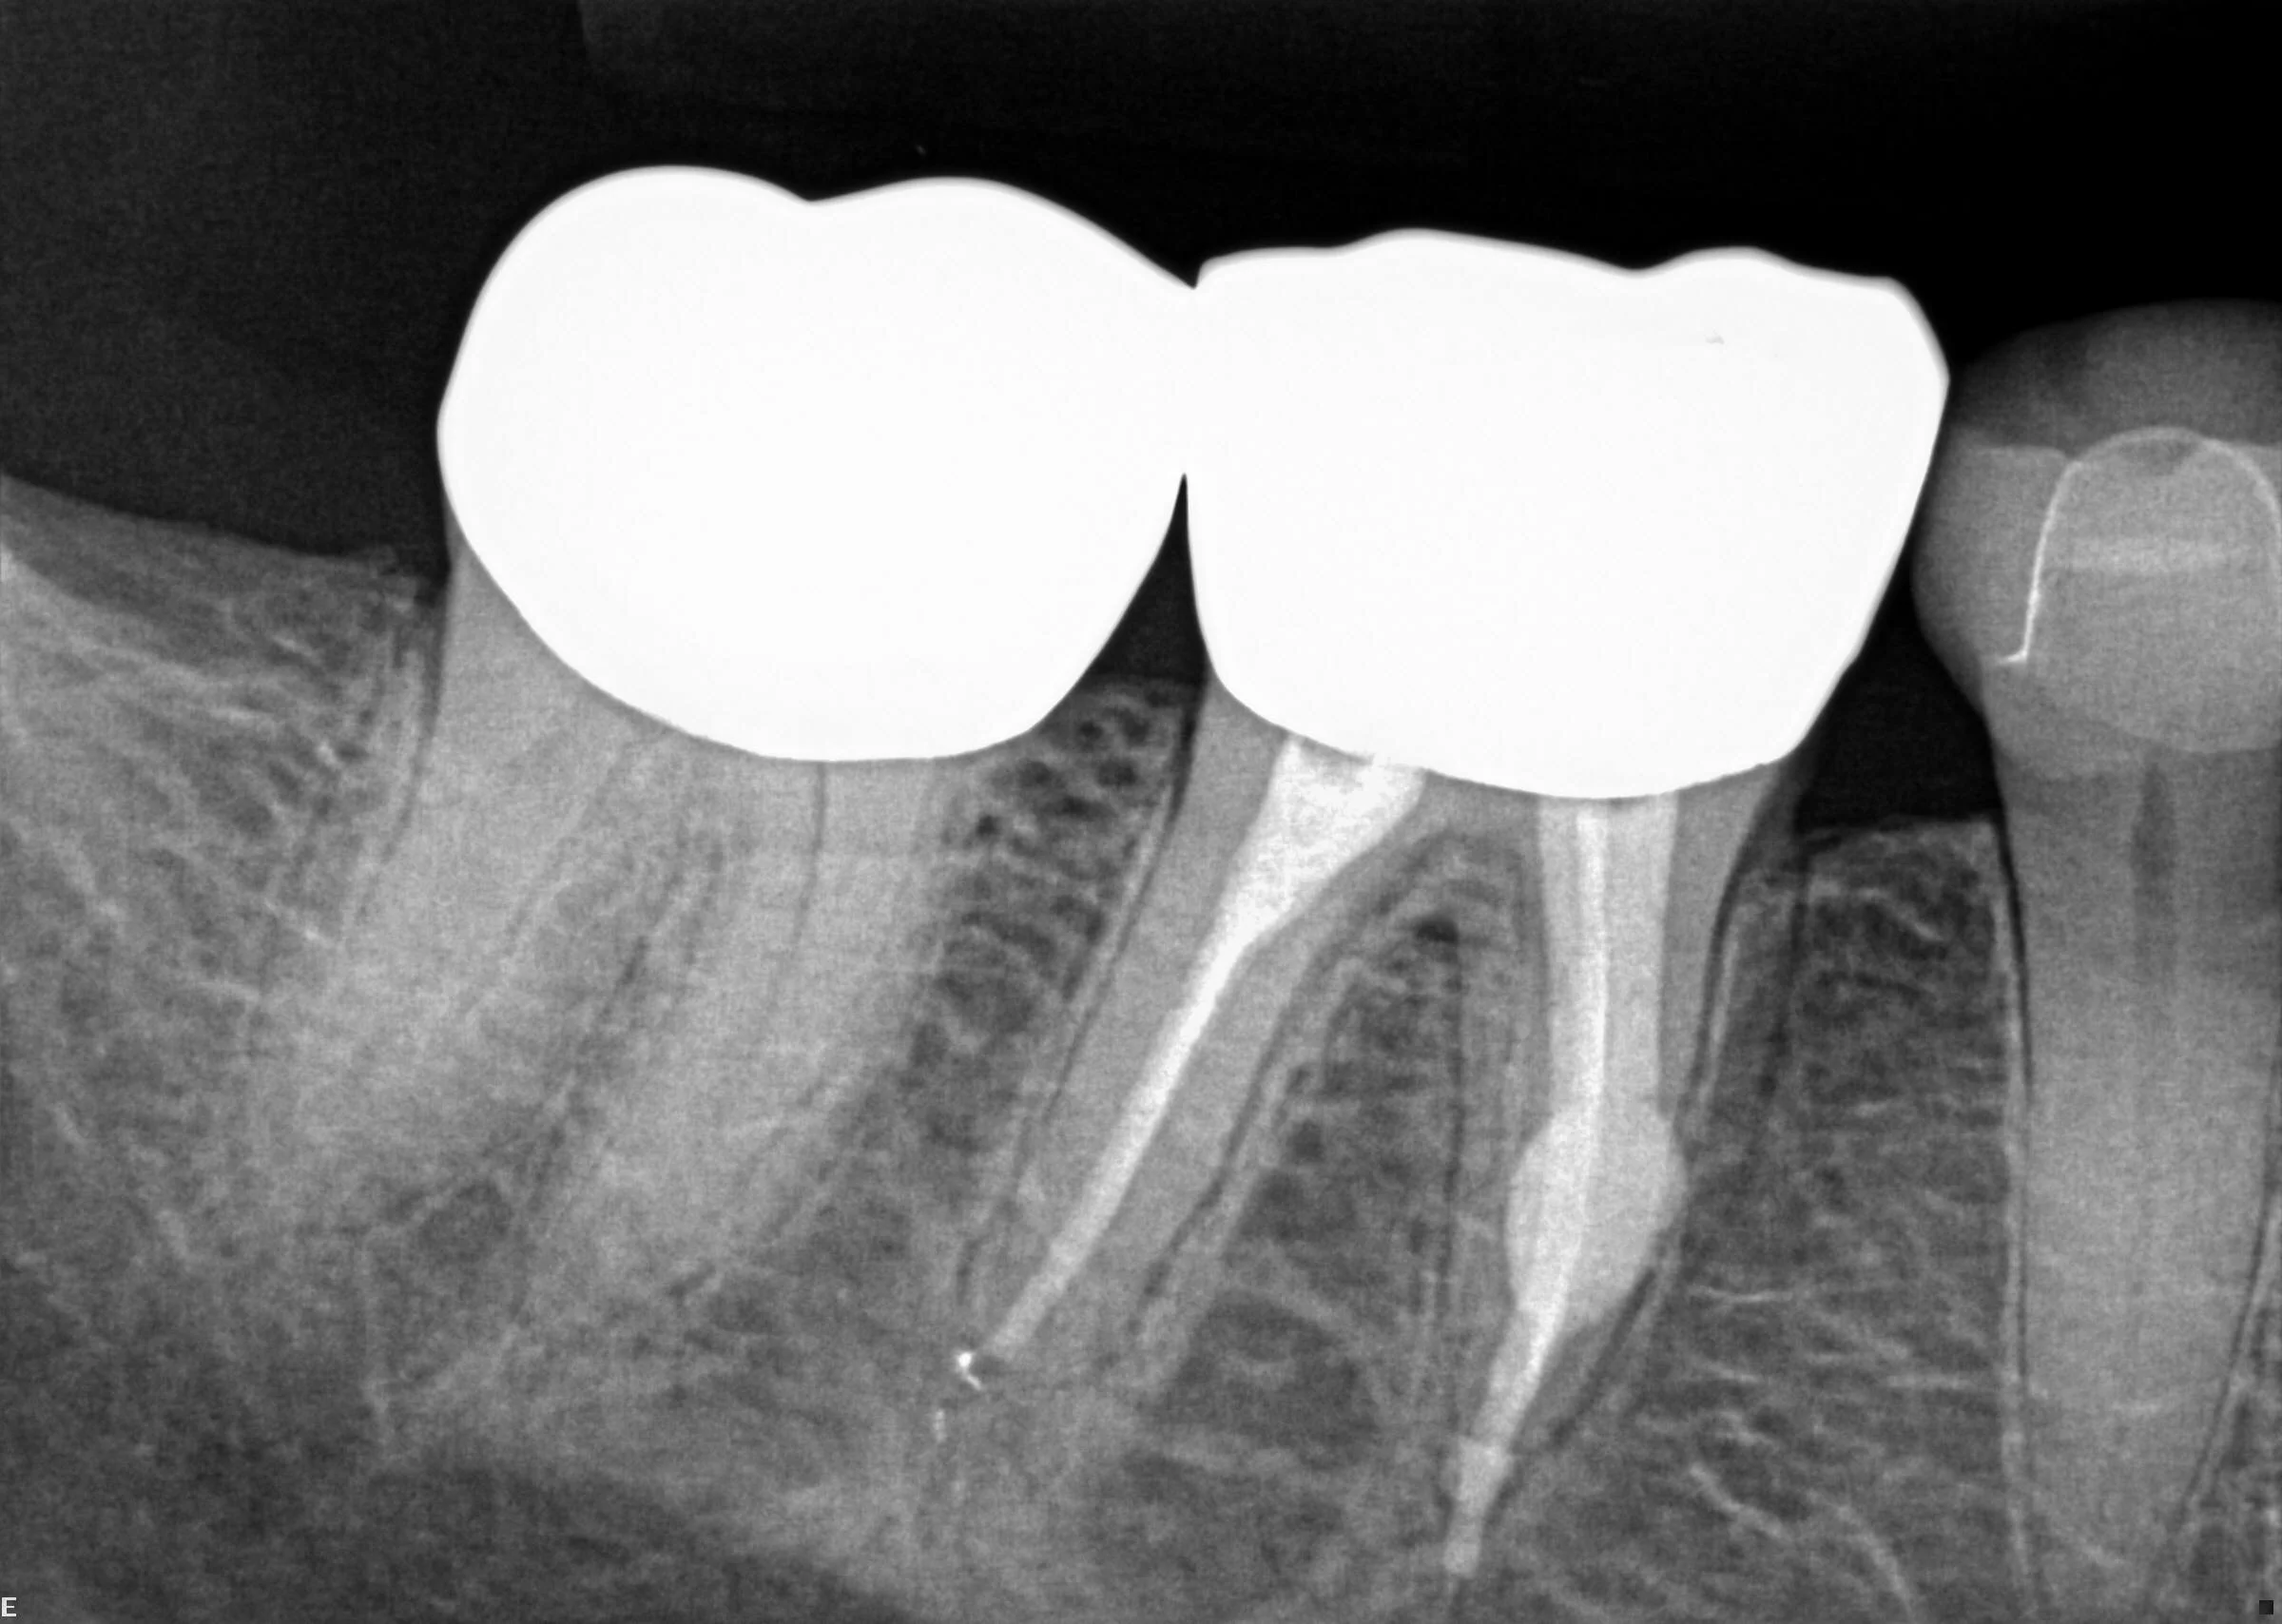

The following example demonstrates how CBCT imagery can assist in diagnosing resorption. In this particular case, internal resorption occurred in both the mesial and distal roots of tooth #30.

Cone Beam Computed Tomography (CBCT) creates 3-Dimensional images that provide detail standard dental radiographs cannot. This allows an endodontist to view teeth from multiple angles, which can reveal anatomical variations or pathology a regular 2-D image fails to disclose. The information contained within CBCT can be invaluable while diagnosing and treating simple and complex cases.

Our CBCT unit utilizes Planmeca Ultra Low Dose™ – a proprietary low dose 3D imaging protocol that enables CBCT imaging with an even lower patient radiation dose than standard panoramic imaging.

This allows capturing an image with a decreased effective patient dose without any significant loss in image quality.